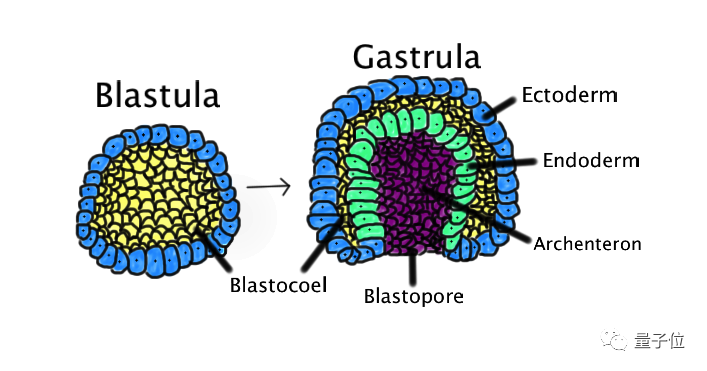

人类胚胎发育有三个过程,经过了受精卵、囊泡之后,就会变成原肠胚。

原肠胚它由三层细胞层构成:外胚层(ectoderm)、中胚层(mesoderm)、内胚层(endoderm)。

之后,各胚层继续伸长,形成前后端,随后进行分化,变成身体的各种组织部位。